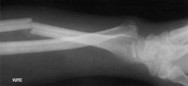

Forearm frx galleass

Gallize Fracture